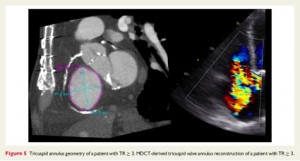

Figure 5(図5: 文献5より引用)

二つ目は前回も紹介した私の論文のsupportをしてくれているPhilippeの論文です。

文献6: van Rosendeal PJ, et al. Eur Heart J Cardiovasc Imaging 2016;17:96-105.

CTによるTricuspid valve remodelingの解析とTRに対する影響に関して述べています。3年前の論文ですが、私がMultimodality imagingの重要性を学んだ論文の一つでもあります。